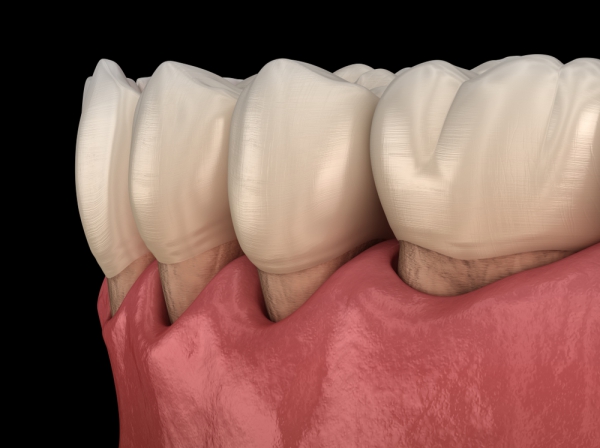

牙周病是漸進式的,初期其實不容易被察覺,不像蛀牙可能會出現疼痛、有孔洞的情形。常見的症狀像是牙齦紅腫發炎,刷牙或使用牙線時容易流血,若放任發炎問題不管,停留在口中的細菌發酵,會導致持續性口臭問題,也會造成牙齦開始萎縮、牙縫變大,牙齒看起來變長,當齒槽骨被破壞到一定程度時,就像房子的地基被掏空,牙齒就會開始動搖甚至鬆脫。